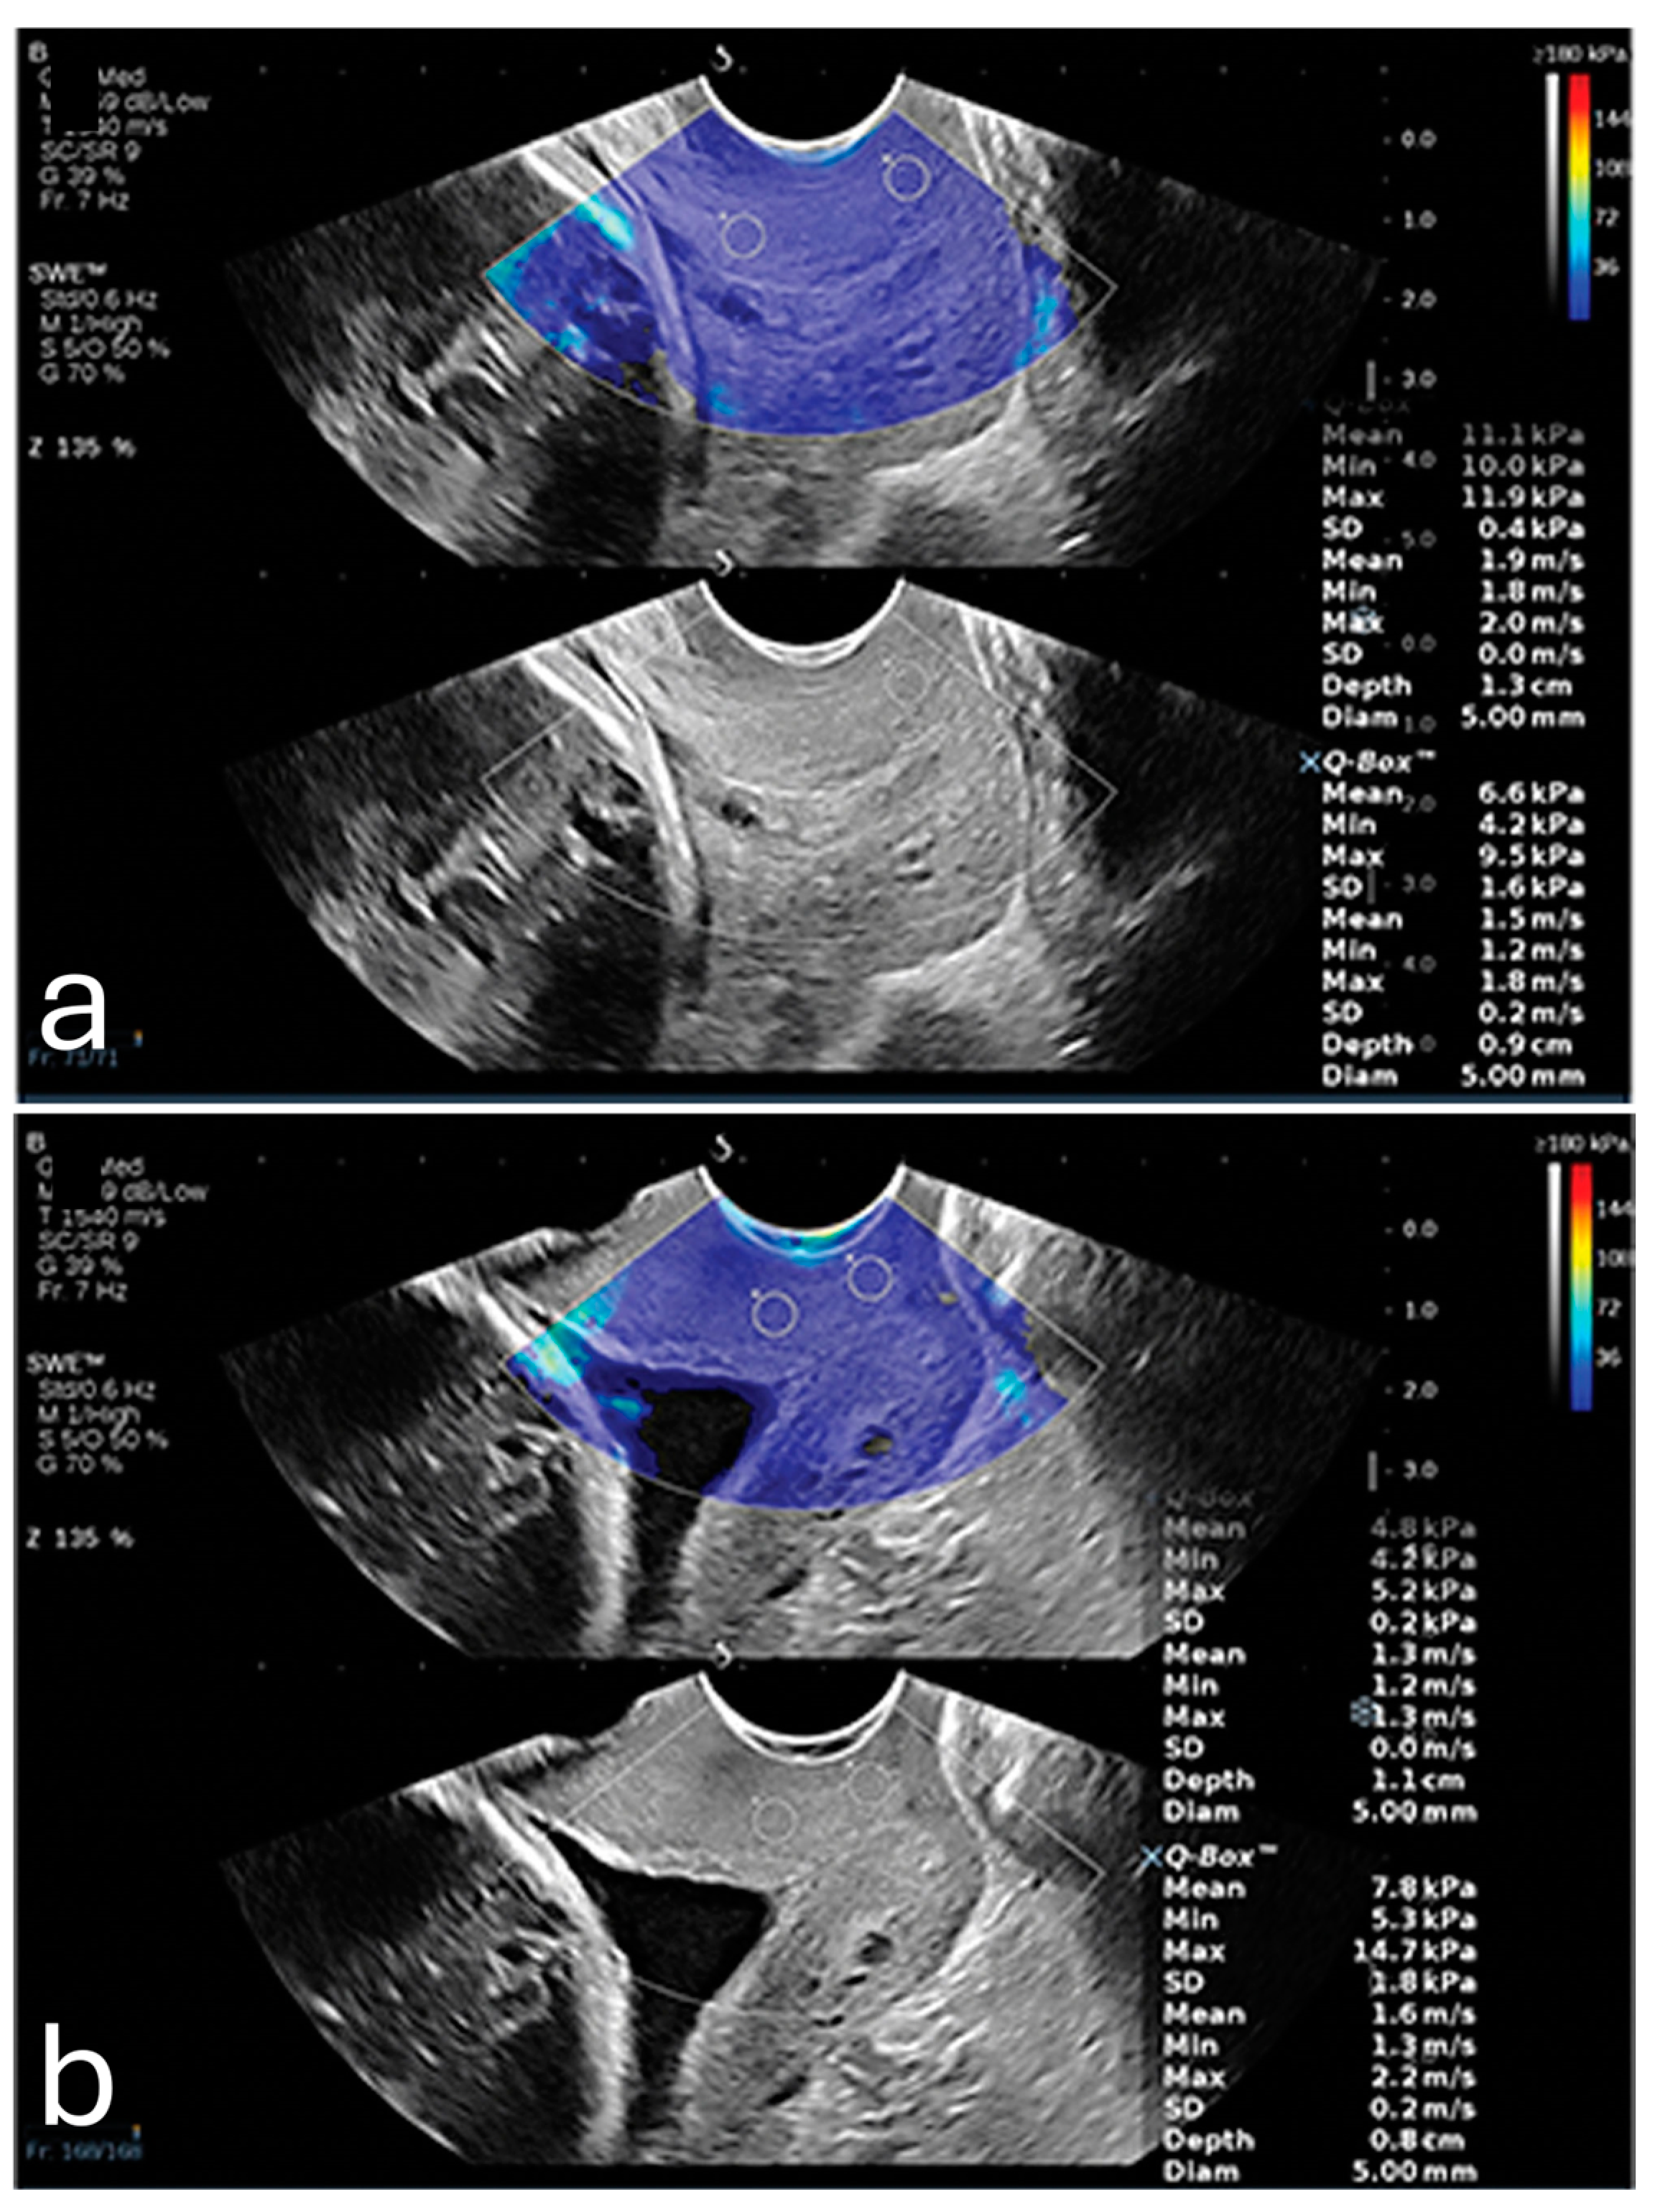

One of the primary factors influencing placental elasticity is the layered arrangement of the chorionic villi, which are densely populated with capillaries and responsible for mediating maternal–fetal nutrient transfer. As trophoblastic cells invade and remodel maternal spiral arteries early in pregnancy, the placental vascular network expands, allowing the tissue to maintain elasticity and accommodate increased blood flow. These vascular adaptations support fetal growth and contribute to the biomechanical softness measured by elastography []. In contrast, elastography detects increased stiffness in cases of placenta percreta, as illustrated in Figure 2 [].

Figure 2. A pregnant woman with placenta percreta showing (a) increased average shear wave velocity (1.95 m/s) in comparison to a pregnant woman with normal placenta showing (b) normal average shear wave velocity (1.83 m/s). Reproduced with permission from Sage. © 2024.

Emerging evidence highlights the potential role of sonoelastography in the evaluation of PAS. A study by Cim et al. used Virtual Touch Quantification (VTQ) techniques, a relatively older generation of elastography, to assess placental invasion anomalies []. They found significantly higher shear wave velocities (SWV) in cases with detected invasion compared to non-invasive cases across all regions of the placenta, with an average SWV of 2.862 ± 0.815 m/s in the invasion group versus 0.926 ± 0.484 m/s in the non-invasion group (p < 0.001) [].

Dokumaci and Uyanikoglu further supported these findings by demonstrating that SWE could differentiate placenta percreta cases from normal pregnancies []. In their case-controlled study, the mean SWV values of the maternal edge of the placenta were 1.95 ± 0.19 m/s for placenta percreta cases and 1.69 ± 0.23 m/s for controls, with a cutoff value of 1.92 m/s, achieving 80% specificity for detecting PAS [].